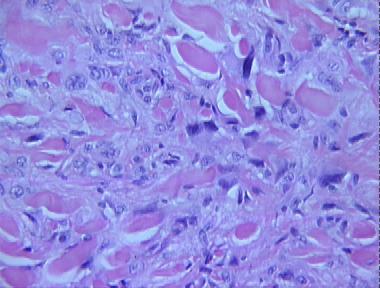

dermatofibroma with monster cells

Histologic Features